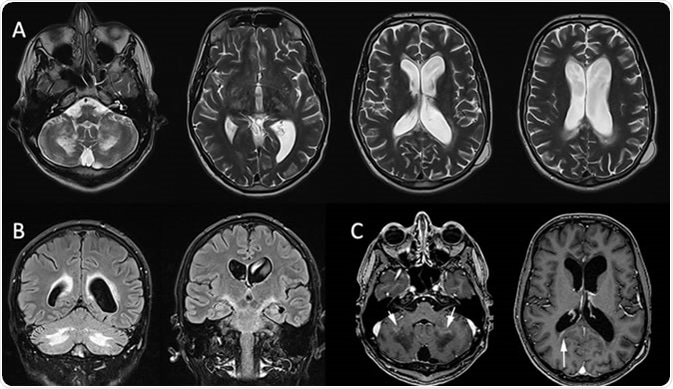

X-linked adrenoleukodystrophy: MRI in a 32-year-old man presenting psychiatric troubles and cerebellar ataxia two years ago. Axial T2-WI (A) and coronal FLAIR (B) show vasogenic edema involving the corpus callosum, the corticospinal tract and the cerebellar WM. Postcontrast Axial T1 (C) shows the inflammatory zone enhances (white arrow). References: -Marseille/FR

X-linked adrenoleukodystrophy: MRI in a 32-year-old man presenting psychiatric troubles and cerebellar ataxia two years ago. Axial T2-WI (A) and coronal FLAIR (B) show vasogenic edema involving the corpus callosum, the corticospinal tract and the cerebellar WM. Postcontrast Axial T1 (C) shows the inflammatory zone enhances (white arrow). Credit: Gilles Brun / Assistance Publique Hôpitaux de Marseille